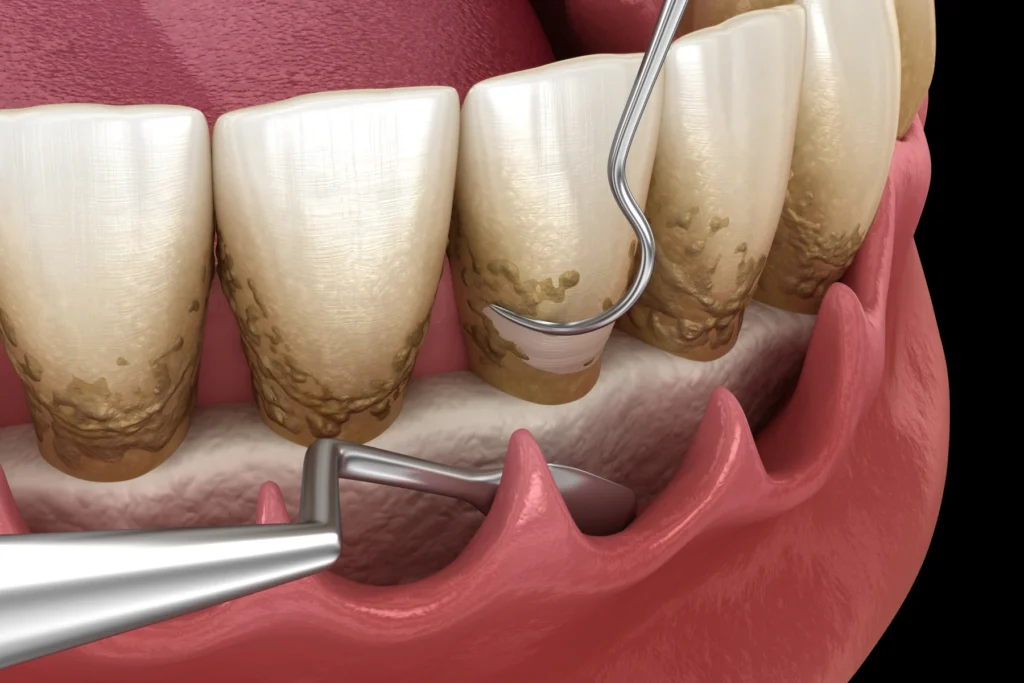

La chirurgie d’assainissement vise à éliminer l’infection persistante. Elle est proposée lorsque les poches parodontales restent profondes malgré les soins initiaux. Cependant, elle intervient toujours après une phase de nettoyage non chirurgical.

Lors de l’intervention, la gencive est délicatement mobilisée. Ensuite, le praticien accède aux racines dentaires. Il élimine le tartre résiduel et les tissus inflammatoires. Ainsi, les surfaces dentaires sont nettoyées de manière précise.

Cette chirurgie permet de réduire la charge bactérienne. Ensuite, elle favorise une meilleure cicatrisation des tissus. Cependant, elle nécessite un suivi régulier. Une bonne hygiène quotidienne reste indispensable pour maintenir les résultats.

Avant l’acte chirurgical, une phase de nettoyage est réalisée. Ensuite, l’inflammation diminue souvent. Ainsi, la chirurgie est mieux ciblée. Cette phase inclut souvent :

- détartrage et surfaçage sous-gingival,